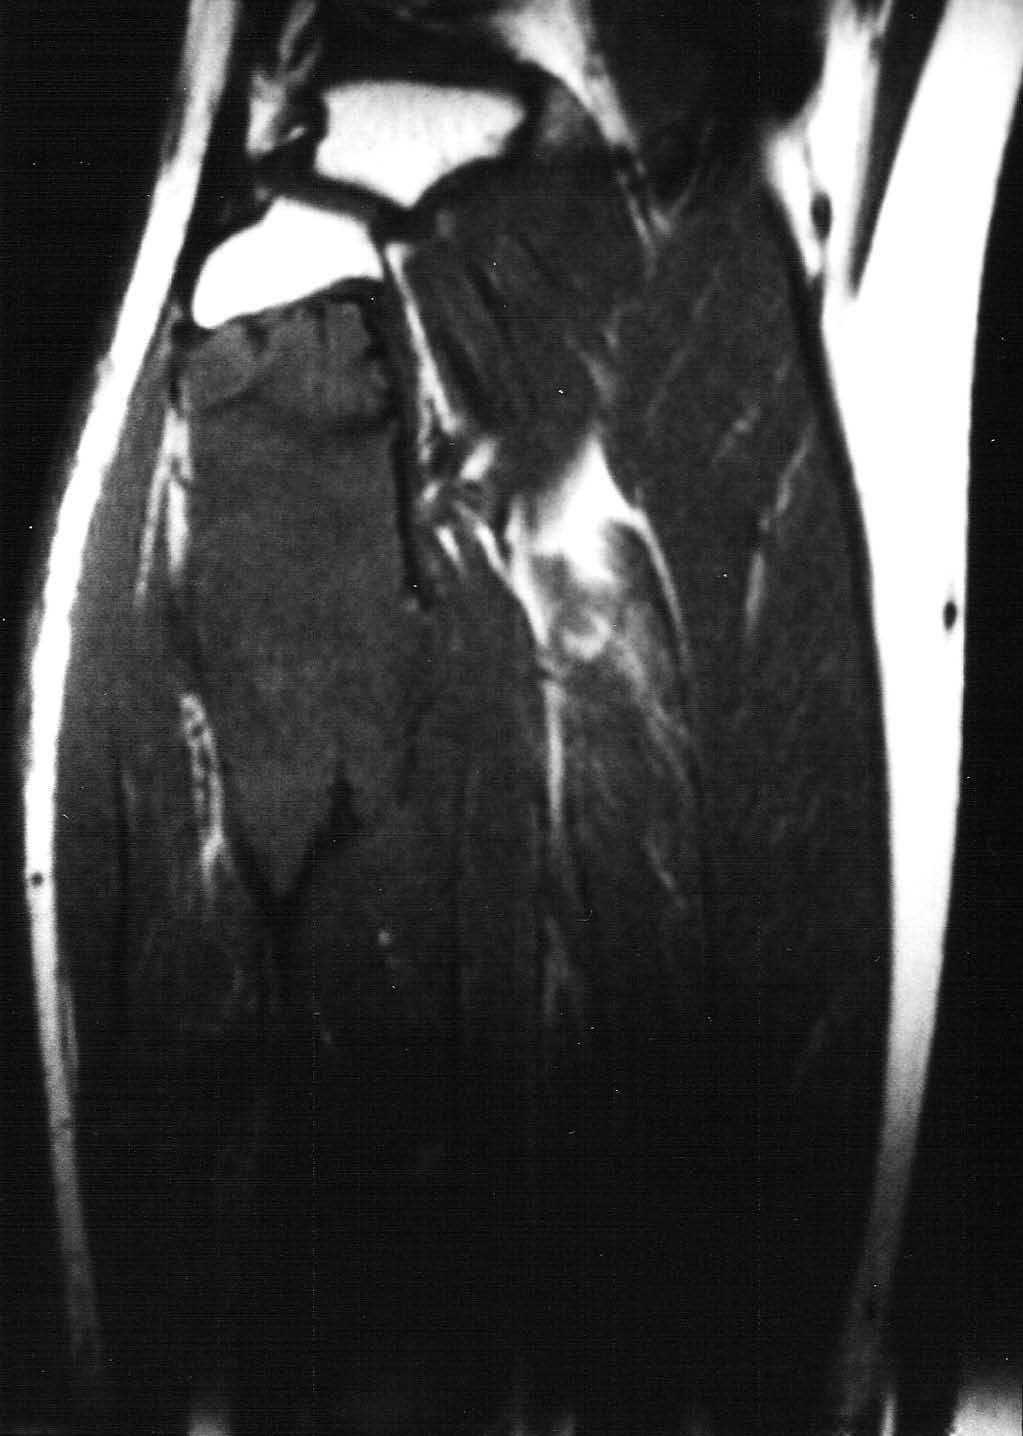

Fig. 5.--Secuencia coronal T1-ES. La lesión aparece homogéneamente hipointensa, de comportamiento expansivo, limitada superiormente por la phisis.

Fig. 6.--Secuencia STIR coronal. Se diferencian los dos componentes. El superior hipointenso con una halo de hiperseñal y el inferior hiperintenso sin asociarse a masa de partes blandas.

La RM permite una clara delimitación entre el hueso normal y el tumoral. Generalmente aparece hipointenso tanto en las secuencias T1 como T2, como los linfomas o los tumores fibrosos, debido a la densa matriz conectiva, y para algunos autores debido a la relativa hipocelularidad, lo que significa una disminución de los protones móviles6. Otros autores recogen otros hallazgos, como la presencia de una pseudocápsula, focos de necrosis, niveles líquido-líquido dentro del tumor8 y, en ocasiones, un comportamiento hiperintenso en las secuencias T22,4. En nuestro caso se identificaban dos componentes diferentes dentro de la misma lesión de diferente señal en las secuencias T2. El componente superior es hipointenso y el inferior de intensidad intermedia. En las secuencias dinámicas postgadolinio intravenoso, el componente superior mostraba un leve realce periférico en fase tardía con prácticamente nulo realce en fase precoz y el componente inferior presentaba intenso realce en fase precoz, que persistía en fases tardías.